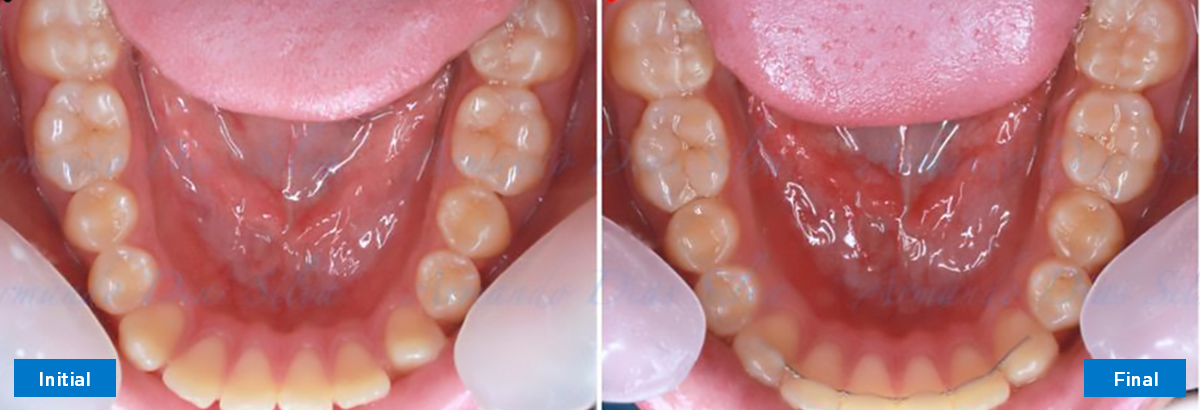

• Alinear y nivelar sin extracciones

• Desrotar y distalizar los molares superiores

• Retruir los incisivos superiores

• Retroclinar los incisivos inferiores

• Sin expansión maxilar, respetando la envoltura periodontal

• Incisivos inferiores retroinclinados, que mejoran la estabilidad a largo plazo